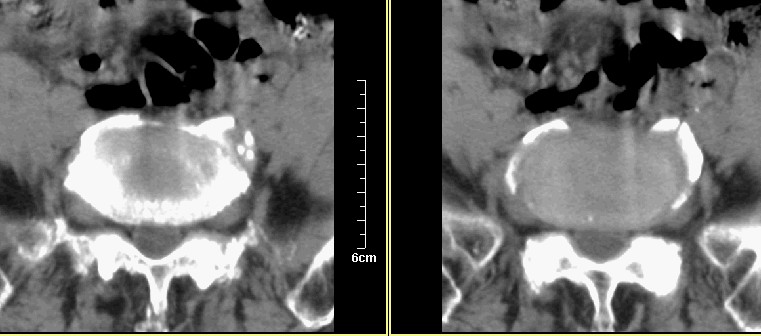

腰1-骶1 间盘及个别椎体扫描

腰3腰4椎体骨质破坏,骨密度低下,骨质疏松,少量骨小梁粗大,紊乱,椎间盘无改变,椎间隙不增宽,椎体无变形,椎旁软组织无肿胀。临床 腰痛明显。考虑:多发淋巴肉芽肿。